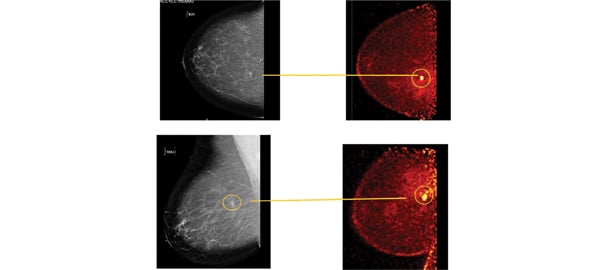

These photos compare the screening mammogram and the diagnostic PEM.

The following case study demonstrates the strength of this PET-guided biopsy approach. A 55-year-old post-menopausal woman presented for routine screening mammogram. Bilateral mammography showed scattered fibro-glandular densities. A new 5 mm irregular spiculated density was seen in the right breast at the 1 o’clock position, 7 cm posterior to the nipple, and evaluated as BIRADS-5, highly suspicious of malignancy. (See photos.) A targeted ultrasound failed to identify the lesion. A biopsy under stereotactic guidance was recommended.

Subsequent organ-specific breast PET or PEM imaging showed a post-surgical rim of 18 F-FDG uptake consistent with granulation at the site of excisional biopsy with modest uptake of FDG. In addition, a 9 mm oval lesion of intense FDG uptake was identified contiguous with the inferior aspect of the biopsy cavity consistent with suspected malignancy. (See photo.) Two adjacent areas of mild FDG uptake were consistent in location and activity with areas of fat necrosis seen mammographically. The patient then underwent one of the first PET-guided breast biopsies as part of a clinical trial.